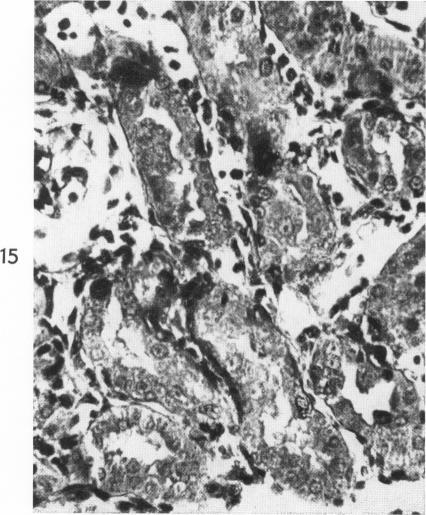

SCARPELLI D G, TREMBLAY G, PEARSE A G

Am J Pathol. 1960 Mar;36(3):331-53.